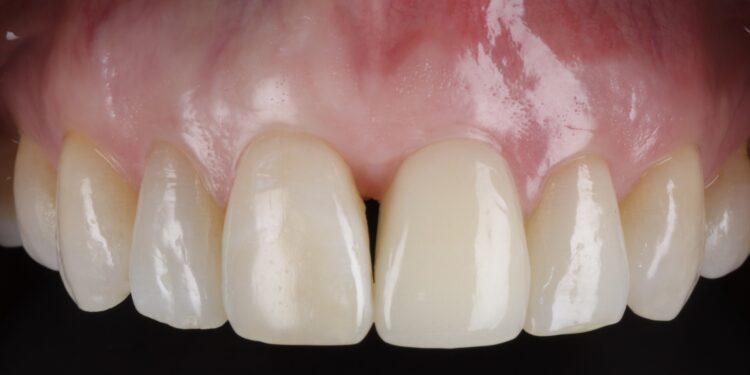

Once the orthodontic treatment was completed, the site was re-evaluated, and it was clear to see that the gingival zenith had significantly improved. The patient was advised that without re-contouring the mesial aspect of the contralateral central incisor there would be a midline black triangle. She rejected the option of composite addition to alter the triangular shape of the UR1 and thus we proceeded to complete the treatment without this. The implant was placed with simultaneous buccal GBR & connective tissue graft following a transmucosal approach. Following a healing period of 4 months, the restorative treatment was initiated with a temporary crown to develop the emergence profile. Once the gingival zeniths had been matched, the patient was delivered a permanent screw retained crown.

This case demonstrates the power of ridge preservation whereby significant hard tissue grafting was avoided entirely in a patient with an extremely thin maxillary alveolus. The improvement in soft tissue contours is evident to be seen even with a healing period of 18 months post extraction with excellent keratinised tissue volume and no distortion in the mucogingival junction.